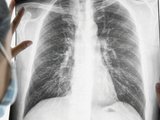

| Khi có các dấu hiệu trên cần đi khám bác sĩ để được chẩn đoán đúng bệnh |